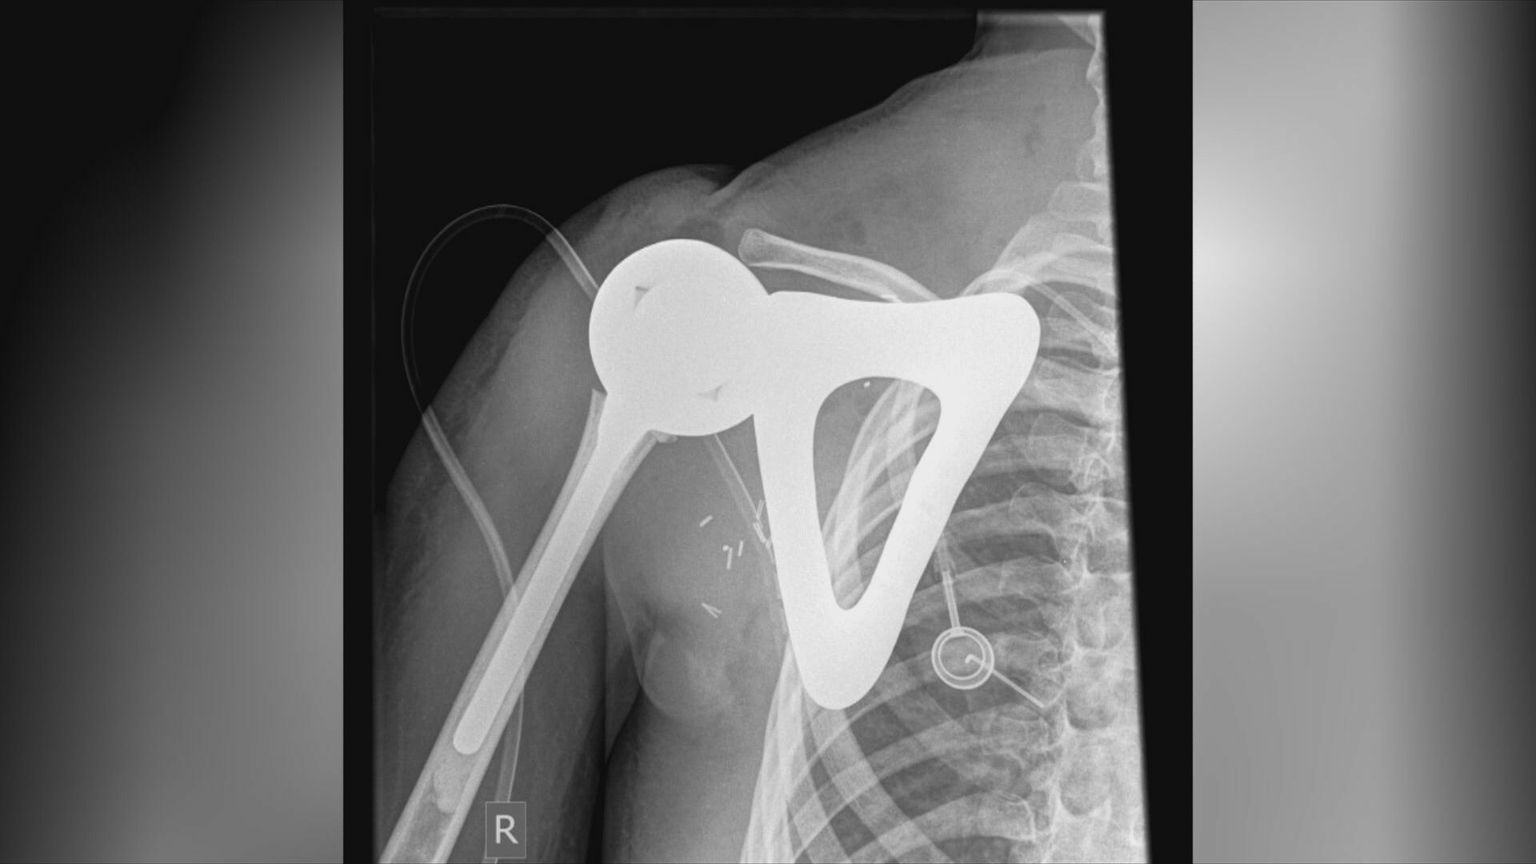

Veliki uspjeh hrvatske klinike: U sedmosatnoj operaciji desetogodišnjaku ugradili novo rame - isprintano 3D printerom

Prvi u Hrvatskoj